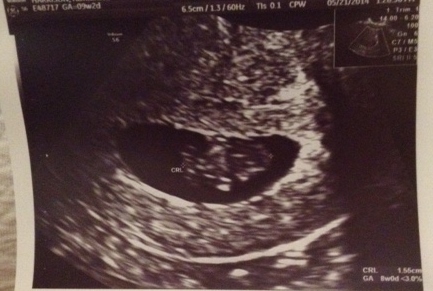

I had my first appointment last Wednesday (I know , I'm late) and it went so well. I got to see bebe and hear the heartbeat (a steady 176), and little lover wiggled according to the sonographer. BF was elated and kept saying "thats so damn cool" They moved my due date to the 31st. so HOPEFULLY i'll be having a baby in 2014. But I guess it doesnt matter what the hell I want lol.

I'll attach a picture of the itty bitty squeesh.